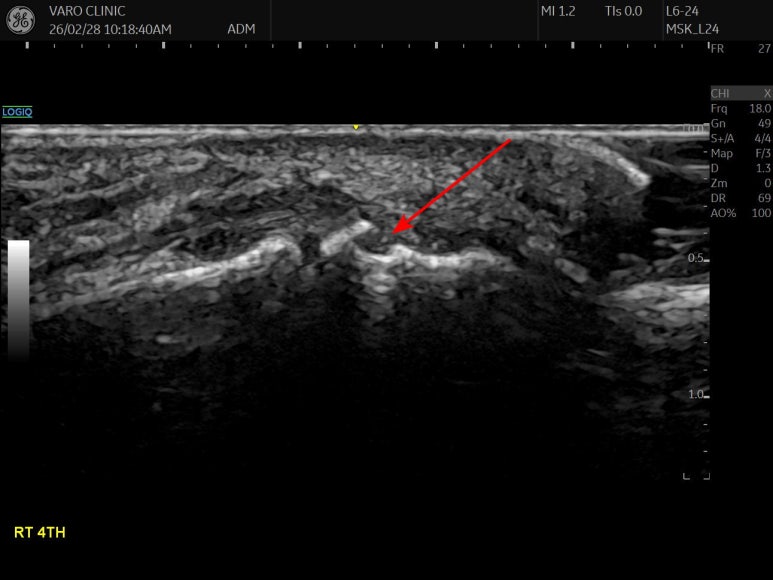

한달이 지나도 통증이 없어지지 않는

네 번째 발가락

협계(俠溪)혈자리를

손으로 눌러보니

딱 아픈 곳이 있습니다.

Step-off sign

네번째 발가락 골피질이 어긋나서 fracture of 4th middle phalanx

솟아오른 모습입니다.

다친 지 4주가 넘었는데

뼈 주변 골막 아래

피가 고여 있고(Hematoma)

주변 조직이 염증으로 부어있습니다.

위쪽 표준 경혈 초음파와 비교해보면

확연히 다른게 보이시죠?

환자분들이 먼저

'어, 저 뼈가 부러졌네요?' 하고

알아보십니다.

프로브를 90도 돌려서

단축 스캔했을 때에도

골절(骨折)이 의심됩니다.